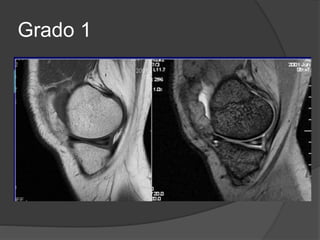

Grado 1

Grado 2

Grado 1  Rotura microscópica

 RM las principales alteraciones son

periligamentosas.

 Grosor y señal de resonancia normal

 Edema y hx periligamentosa